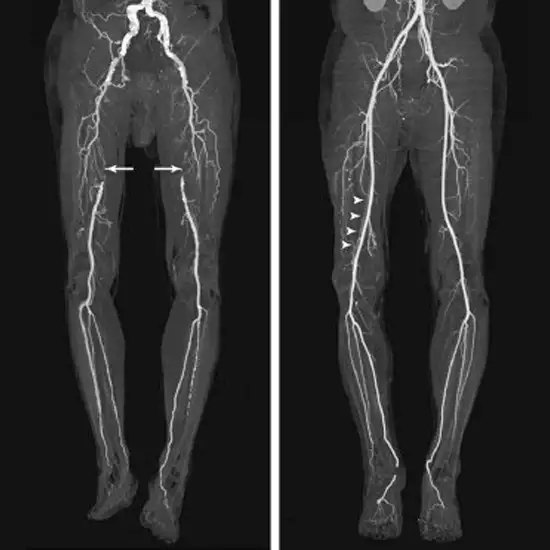

A CT Angiography Left Lower Limb is an imaging test in which a contrast medium is used to diagnose the vascular injury of the left lower limb.

In this procedure, you need to lie supine on a table and your legs are placed towards the gantry. A cannula is inserted in your arm and then dye is injected through a cannula ( 90-100ML) while performing the scan.